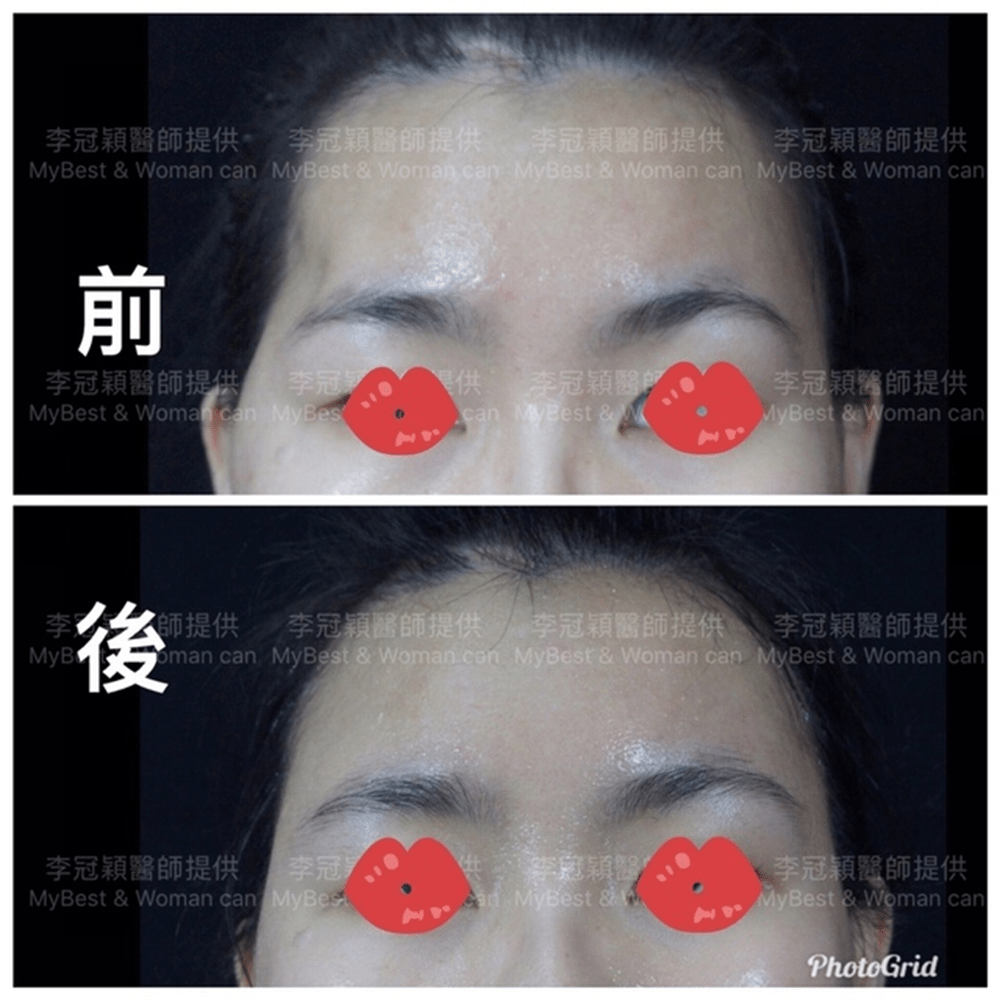

前 後(三個月)太陽穴到側額凹陷,眼尾下垂。(太陽穴不對稱往往來自顴骨大小不對稱)可以調整改善對稱性。

臉型不對稱 在太陽穴有一定落差,上圖經過太陽穴墊片矯正後,也明顯改善不對稱的視覺效果。重要的一點可以支撐眼尾下垂,改善老態眼神!(上圖)經內視鏡墊太陽穴跟提眼尾術後滿意。

(下圖)凹陷太陽穴,提前老態與眼尾下垂,經李醫師內視鏡太陽穴墊片支撐眼尾,幾乎不鬆垂完全抗老。

下圖:太陽穴墊片後兩年,眼尾支撐效果持久。